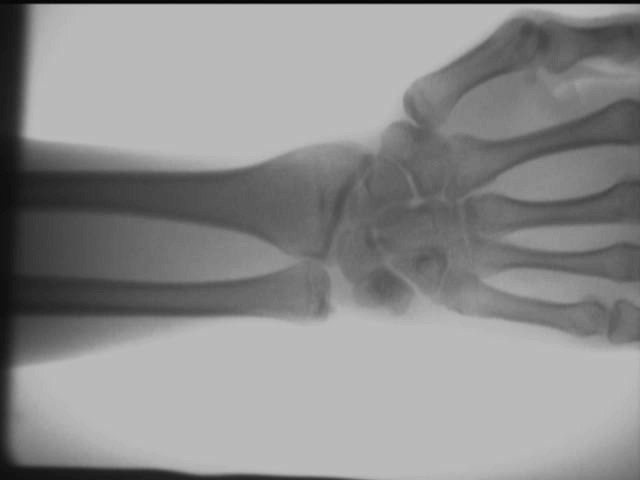

Tenyér perspektíva hatás

Kéz boka ízületi hatás

Kar ízületi hatás

A fenti vizsgálati eredményeket a helyszínen, AS-C200 segítségével kapjuk meghordozható röntgenkészülék